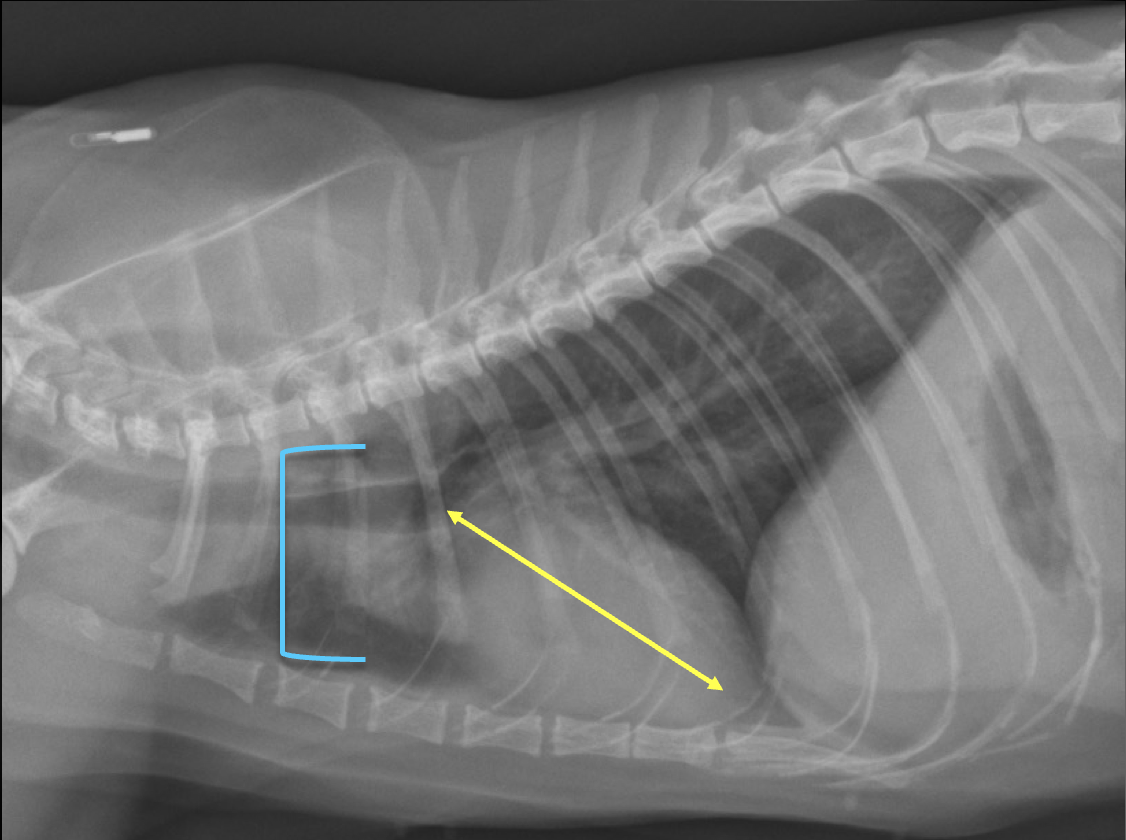

What is shown in these images?

right heart failure -enlarged caudal vena cava -hepatomegaly -ascites